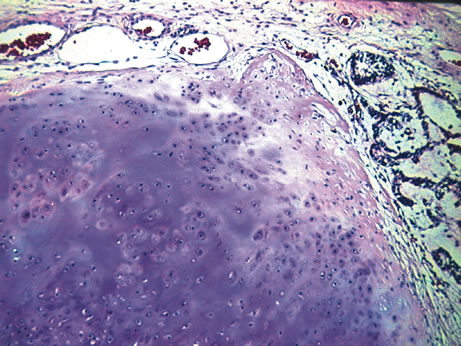

Inflammatory conditions may also lead to iris nodules. Patients suffering from fungal endophthalmitis may demonstrate an irregular yellow-white mass on the iris. Histologically, these appear as necrotizing granulomas containing mycotic agents (Fig. 2). In juvenile xanthogranuloma, a yellowish-gray iris lesion may be associated with spontaneous hyphema, and histopathologically the nodules demonstrate diffuse histiocytic infiltrate (Fig. 3). Multinucleated giant cells displaying peripheral foamy cytoplasm are also noted; these cells are known as Touton giant cells.29 The giant cells and the histiocytes contain lipid that can be demonstrated by oil red O stain.

Fig. 3. Juvenile xanthogranuloma. The iris is infiltrated by histiocytes, which form nodular aggregates on the anterior surface of the iris. (Hemotoxylin-eosin ×25.) Inset (×200) shows oil red O-positive histiocytes.